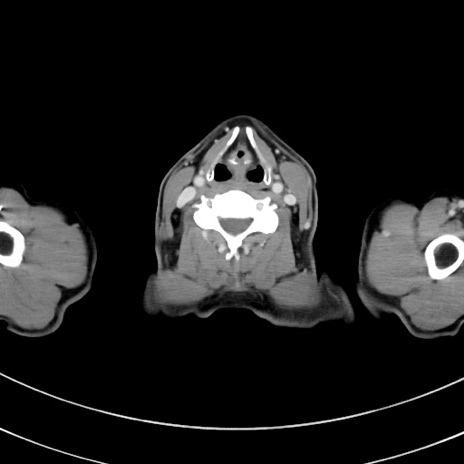

症例8(横断像)

【症例】 60歳代男性

【主訴】 黒色吐物

【現病歴】 4日前から嘔気自覚、2日前の朝食後にも嘔気あり、自分で手で嘔吐反射起こし嘔吐したところ血が混ざっていたため受診。

【既往歴】 5年前汎発性腹膜炎を伴う急性虫垂炎で手術、高血圧、前立腺肥大症、高脂血症

【身体所見】 腹部正中に手術癩痕あり 腹部平坦・軟圧痛なし膨満感あり

【データ】WBC 8400、CRP 4.54